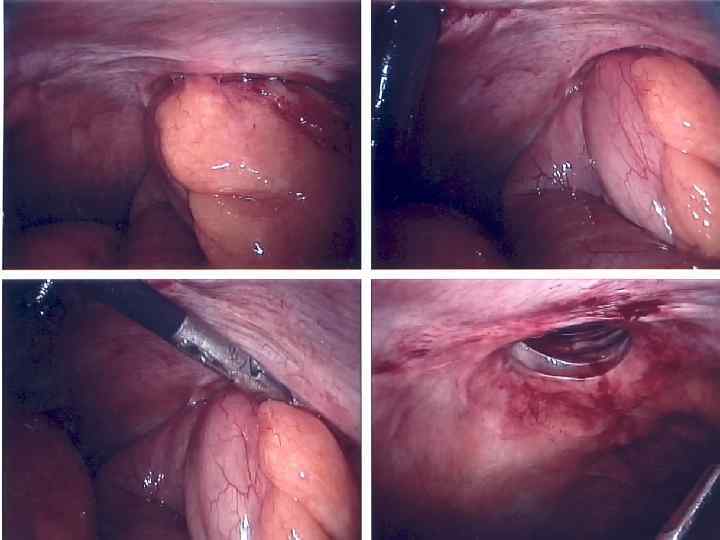

ЭТАПЫ ОПЕРАЦИИ ПРИ УЩЕМЛЕННОЙ ГРЫЖЕ • Рассечение кожи и подкожной клетчатки • Обнаружение дна грыжевого мешка без широкой мобилизации • Вскрытие грыжевого мешка • Фиксация ущемленного органа • Рассечение ущемляющего кольца • Оценка жизнеспособности ущемленных органов

ПРИЗНАКИ НЕЖИЗНЕСПОСОБНОСТИ КИШКИ • окраска – багровый или черный цвет • отсутствие пульсации краевых сосудов брыжейки • отсутствие перистальтики

ОСЛОЖНЕНИЯ УЩЕМЛЕННОЙ ГРЫЖИ • Флегмона грыжевого мешка • Острая странгуляционная кишечная непроходимость

УЩЕМЛЕННАЯ ГРЫЖА С ФЛЕГМОННОЙ ГРЫЖЕВОГО МЕШКА • Лечение – экстренная операция • Особенности – пластика не производится